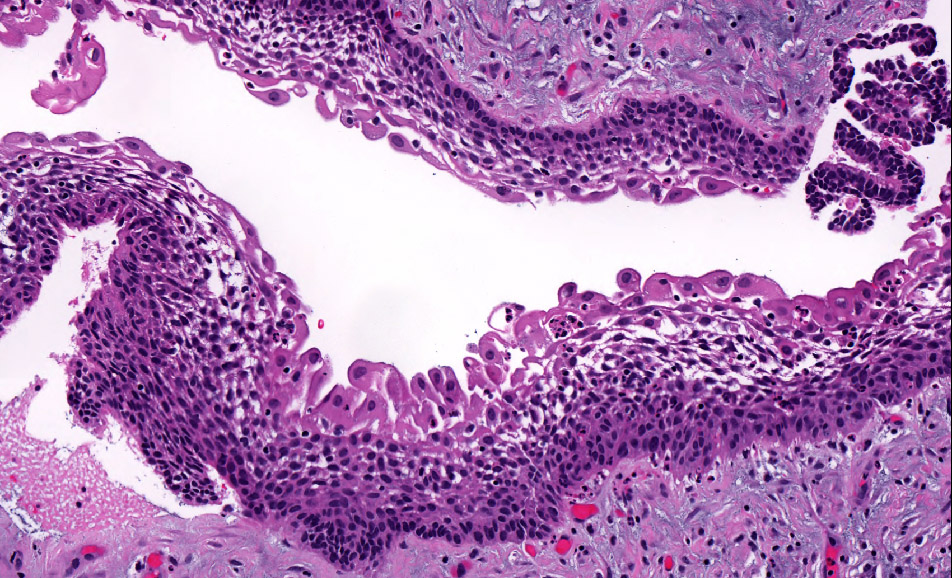

Microscopic (histologic) images

Contributed by Kelly Magliocca, D.D.S., M.P.H. and Anne C. McLean-Holden, D.M.D., M.S.

- Within the epithelial islands and cords of conventional ameloblastoma and the cystic epithelial lining of unicystic ameloblastoma, the odontogenic epithelium shows similar changes:

- Columnar cells with hyperchromatic nuclei at basal layer, exhibiting peripheral palisading

- Cells show reverse polarization away from basement membrane (Vickers-Gorlin change)

- Subnuclear vacuolization

- Suprabasal cells with a loose, network-like arrangement, recapitulating stellate reticulum formation seen in normal odontogenesis

- Follicular: most common subtype; islands of odontogenic epithelium in fibrous connective tissue; may be cystic; classic peripheral palisading and stellate reticulum-like areas

- Plexiform: cords and sheets of anastomosing odontogenic epithelial cells; classic peripheral palisading and reverse polarity not always obvious